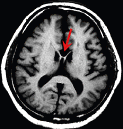

みなさん女性と男性では、脳の構造が違う!という話は聞いたことがあると思います。 左脳と右脳の間は「脳梁(のうりょう)図1」という神経線維の束で繋がっており、女性はその「脳梁」が男性よりも太いので、男性よりも左右の連携が良いらしいです。